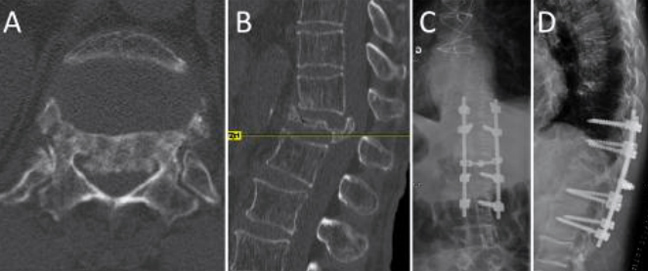

Σε περιπτώσεις με βαρεία πάθηση των πνευμόνων ή της καρδιάς, συνιστάται η λήψη αναλγητικών για διάστημα τριών μηνών, οπότε το κάταγμα έχει κολλήσει. Σε όλους τους άλλους η θεραπεία είναι η έγχυση ακρυλικού τσιμέντου (κυφοπλαστική) που σταθεροποιεί τον σπόνδυλο και περνάει ο πόνος αμέσως.

Τα κατάγματα της θωρακικής μοίρας της σπονδυλικής στήλης από ατύχημα συνήθως χρειάζονται χειρουργική αντιμετώπιση (σπονδυλοδεσία).